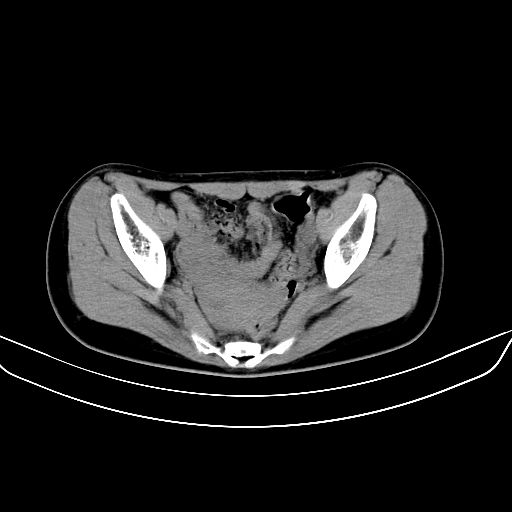

以下是引用zsl6918在2008-7-11 21:40:00的发言:[br]双侧骶髂关节骨质破坏以下三分之一为主,符合强直性脊柱炎表现

以下是引用zhangzhongshou在2008-7-11 21:41:00的发言:[br]患者是女性,hla-b27抗原(—),首先不太考虑强直性脊柱炎,建议查类风湿因子,骶髂关节改变考虑类风湿性关节炎可能性大,建议进一步检查。